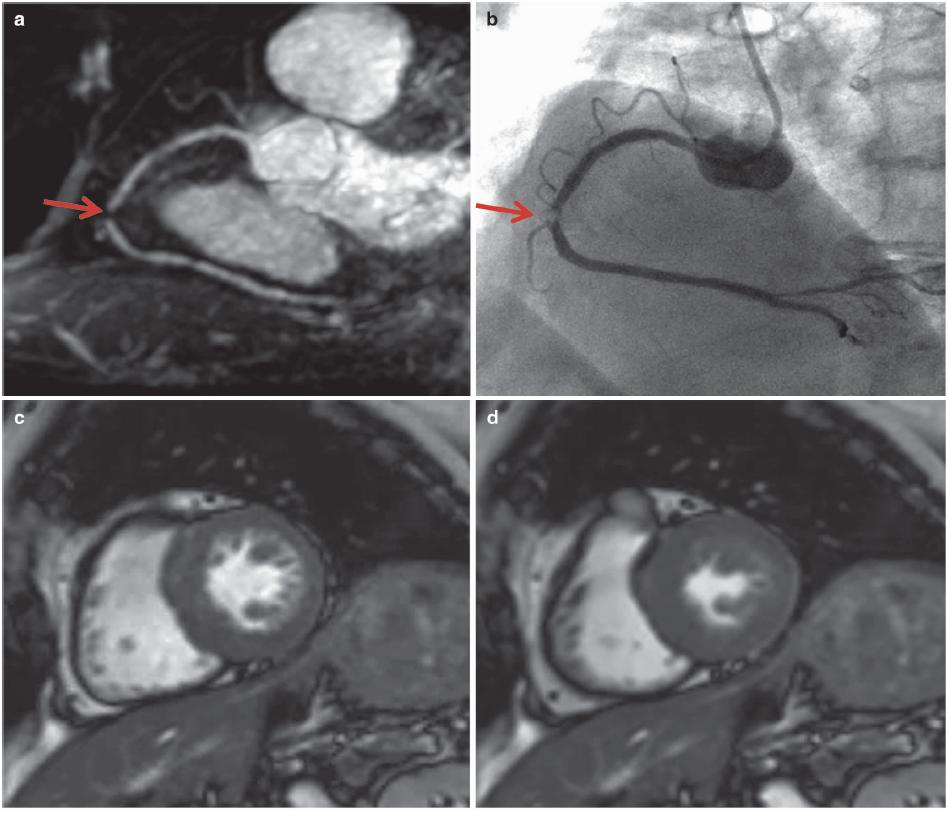

图7.6 心肌缺血,LAD明显狭窄。患者男性,40岁,胸痛。1.5T MR获得非对比增强的三维CMRA图像,采用稳态自由进动(SSFP)序列、导航回波门控、T2预扫描、光谱预饱和、反转恢复脂肪饱和(TR/TE,4.6/2.3ms;翻转角度,90°;SENSE因子4;FOV 280mm×280mm×120mm;采集矩阵256×256×80;重建矩阵512×512×160)。

(a)全心冠状动脉MR血管造影MIP图像显示LAD近段重度狭窄或闭塞(箭头)。(b,c)后降支(PDA)也有明显狭窄。(d-f)冠状动脉MR血管造影和冠状动脉造影(箭头)之间有良好的一致性。(g)舒张末期的短轴电影MR图像,(h)收缩末期未见明显的区域性室壁运动异常。(i)晚期钆增强MR图像未见心肌瘢痕。(j-l)负荷和灌注MR图像显示前间壁严重缺血(箭头),与LAD供血区对应。